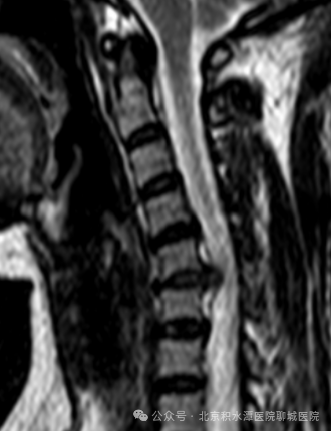

病史:患者5个月前无明显诱因出现左上肢放射性疼痛,活动时加重,休息可稍有缓解,于当地卫生室膏药治疗,症状未见缓解且逐渐加重,出现左前臂麻木、无力,手指不灵活,同时肌力下降、提物困难,于当地中医院行针灸治疗,症状仍未缓解,行颈椎MRI示:颈椎间盘突出伴神经根病。辗转多地医院,治疗方案为颈椎前路椎间盘切除减压植骨融合内固定术。患者拒绝开放手术治疗,来我院要求行微创手术,遂收入院。

术前影像:C5/6椎间盘向左后方突出,压迫神经根

术后影像:去除C5/6左侧椎管背侧少量骨质

进行减压并摘除突出的间盘组织